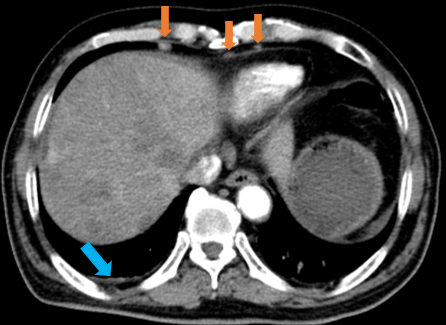

Hình 1: Hình ảnh chụp CT lồng ngực: Nhu mô thùy dưới phổi trái sát rốn phổi có nốt kích thước 24x26 mm bờ không đều, sau tiêm ngấm thuốc (vòng tròn đỏ), hình ảnh cắt cụt nhánh phế quản thùy dưới.

Hình 2: Ít dịch khoang màng phổi phải dày 5 mm (mũi tên xanh), Vài hạch góc tâm hoành hai bên, đường kính lớn nhất 10 mm (mũi tên cam)